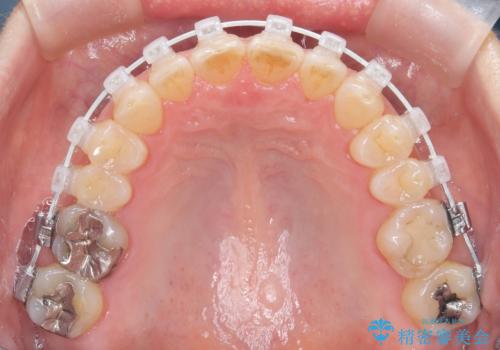

今回の矯正治療では、歯の色に近い目立たない審美ブラケットとワイヤーを使用しました。

スペース確保のために、まず奥歯全体をわずかに後方へ動かす遠心移動を実施し、前歯を並べるためのスペースを確保。さらに、安全性に配慮しながら歯の側面をわずかに削るIPRを併用し、デコボコを解消しました。

ワイヤー矯正ならではの確実な歯のコントロールにより、当初の計画通り約1年という短い期間で、前歯のガタつきが解消。見た目が美しく整っただけでなく、清掃しやすい機能的な歯並びを獲得していただけました。